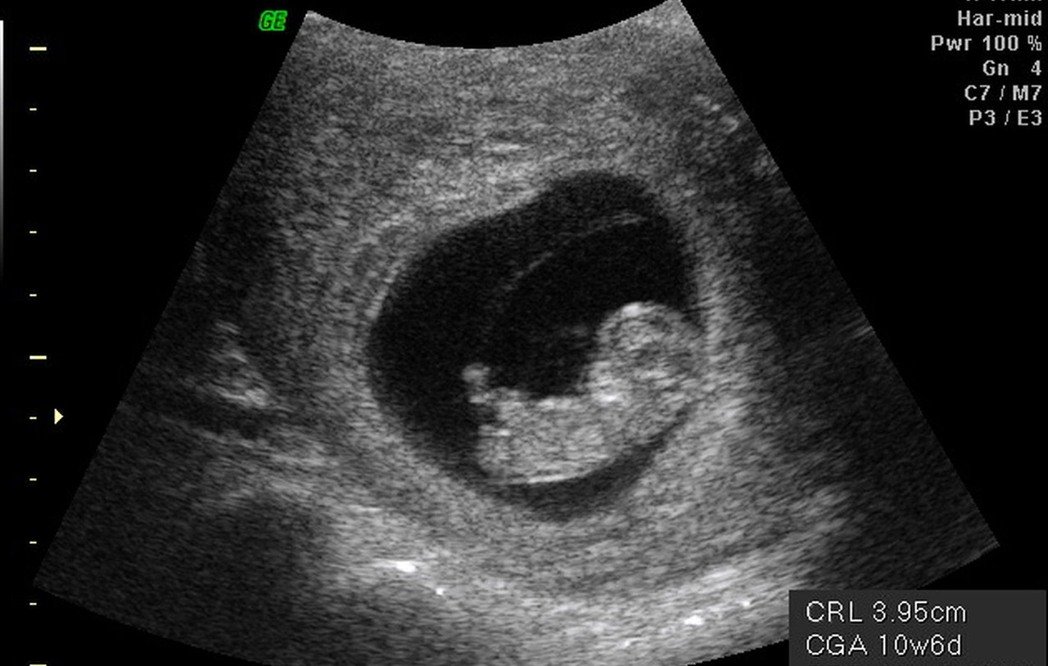

到底為什麼懷孕未滿3個月不能說?許多人都以為是迷信,但婦產科醫師蘇怡寧說出了她的想法:「是有一定的道理在的!」

婦產科醫師蘇怡寧在臉書發文:「為什麼習俗都告訴我們懷孕三個月以前都不要說呢?關於這件事情我必須說,這種說法確實還是有一定的道理在的,無關迷信,而是一種對於人生不確定性的敬畏。」

蘇怡寧說:「統計上大約有三分之一到5分之一的胚胎,在12周之前,也就是三個月前會自然淘汰掉」「所以在真實的世界中,如果你太早告訴人家懷孕了,如果你真的不幸遇到在三個月之前流產了,接下來的日子遇到朋友不間斷的關心,那可能是一次又一次的錐心之痛,當然至於誰該說誰不該說,就得自己拿捏喔。」

「在情感上,三個月內盡量低調不要公布,或者,盡量不要揭露人家早期懷孕的訊息,多給些體諒、多留些空間、少給些壓力。

多給些體諒,多留些空間,少給些壓力,我想,這會是很貼心的事。」